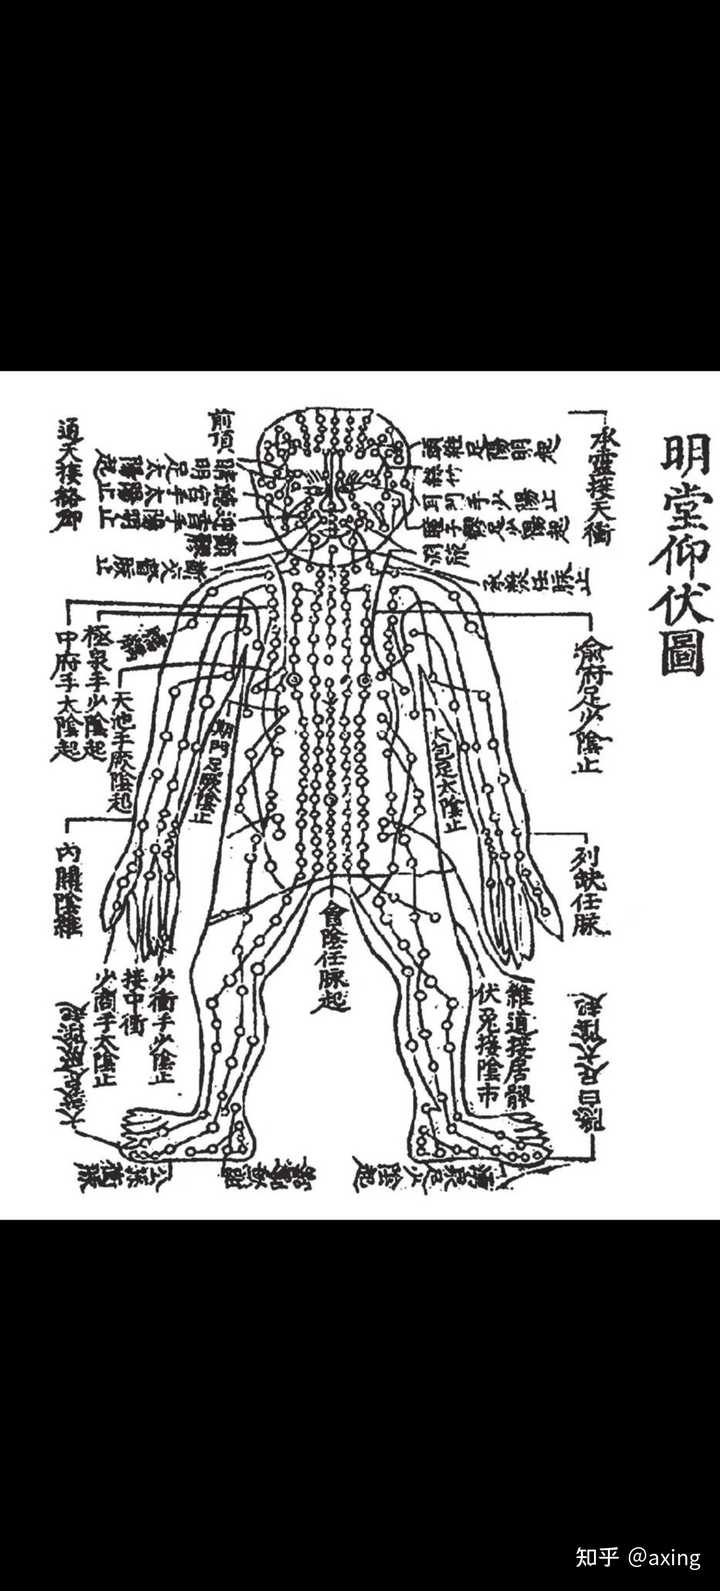

�������辭��ͼ ����ͼ������������ġ�ҽѧ���š����Ұ����ž���ͼ��Ϊ�Ȿ���ͼ��ʾ������һ����������Ϊ�Ҹо�������Ծ����м�����о�����һ��Ҳ�������ܹ����Ǵ��������Բ��ܰѾ���ͼ�������������֡� ���Ƶ��ھ����������磬������Ѫ��Ӫ�����������Ǿ������Ҫ���ܡ���������������Ӫ�����е���Ѫ����������뿴��ϸ�ˣ����イ�ģ�����֤�в��ܹ۲쵽�������������������۾����ܿ�����ѪҺ����������֤�ĺ�һ�������Ǹ���ģ���Ȼ���dz��з��ģ���Ҫ������������������ѪҺ������Ҳ����������Ѫ���Լ��ܹ����Լ��𣿿��������ϣ��Ӷ���ֱ�����࣬���û�п�ѧ�ļ�ܣ��ĸ����Ǽ����Ե��� ����˫����ͼ �����л�������һ������Ķ��������ֶ�������ʲô�õģ���֪����ֻ֪�����Ŵ����о��߰����������������������˾�Һ�ľ����Ǿ�������Ǹ������������������ϵ������������д����ش����ž��� �����۲쵽������ʢ���˾���������ɫ�ĸ�״����Ө��������Ȼ������һ�����ʡ����־�����Ҳ���ޣ�û�����塣������������۲죬Ѩλ�ı����Ǹ���̬Բ�εĶ���������ˮ����Բ���������ӣ���ת�˶����ˣ�������������ʱ��������һ�����塣Ѩλ�������Ǹ��������ʹ��ɵ�Բ���塣��������Ҫע����ǣ������ʵĶ�������̬�����м����ӵı仯��ѨλҲ�����⡣�μ�̫�����پ��IJ�ͼ�� �������� 2.һ��Ѩλ�ж��Ѩλ�� Ѩλ��һ�����߶��Ѩλ�ڡ��е�Ѩλ��һ��Ѩλ�ڣ��е�Ѩλ�ж���Ѩλ�ڣ��еĻ������������ĸ�Ѩλ�ڣ��������и����Ѩλ�ڡ� ���Ѩλͼ ��ЩѨλ�ڣ�������Ƕ��ֲ�ͬ�ľ��硢����������������Щ���ӵ�Ѩλ�ڣ������ܸ��ӵ��������͵���ˮ�ܵ��Զ������š����ء� ѨλҲ��������Ȼ�����������صľ��������ڵ������侮�������ţ�֪�����ģ������ۿ������� Ѩλ����״ 3.Ѩλ�ھ��ж�����״ ������Ƥ�������Ѩλ�ڣ�����Ȩ����������̽����һ���������Ρ����Ρ������Ρ�Բ�Ρ�÷���Ρ����Ρ�Ѩλ�ڵ�������죬���ܱ�־�����Ǹ��Դ�������������Ϣ��ͬ������������ṹҲ��ͬ�� ��Ѩλ�ڱ������״�����ǻ���Ҫ��ܶ��ʺţ�Ϊʲô����������һѨһ��״������һѨ����״��������״��Ѩλ����ʲô���ã� 4.Ѩλ�е����� Ѩλ��ͻ�����ص㣬��Ѩλ�����������������������˶�������ת�ģ���˳ʱ�����ʱ�����������������ж���˶����� |